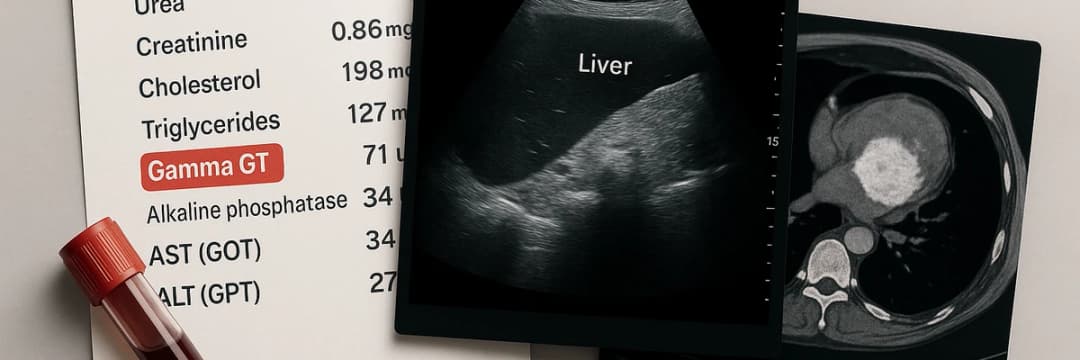

Gamma GT à 100UI/L : est-ce grave ? Causes, fatigue associée et que faire

Gamma GT à 100 : est-ce grave ? Causes possibles, fatigue associée, risques pour le foie et solutions concrètes pour faire baisser durablement vos Gamma GT.

Faire baisser ses Gamma GT naturellement : durée, méthodes et erreurs à éviter

Gamma GT élevées ? Découvrez comment les faire baisser naturellement : méthodes, durée, erreurs à éviter et accompagnement avec Option Zero.

Quels examens demander en cas de Gamma GT élevé ?

Gamma GT élevé : analyses, imagerie et suivi médical. Découvrez les examens indispensables pour identifier la cause et agir sur votre santé.